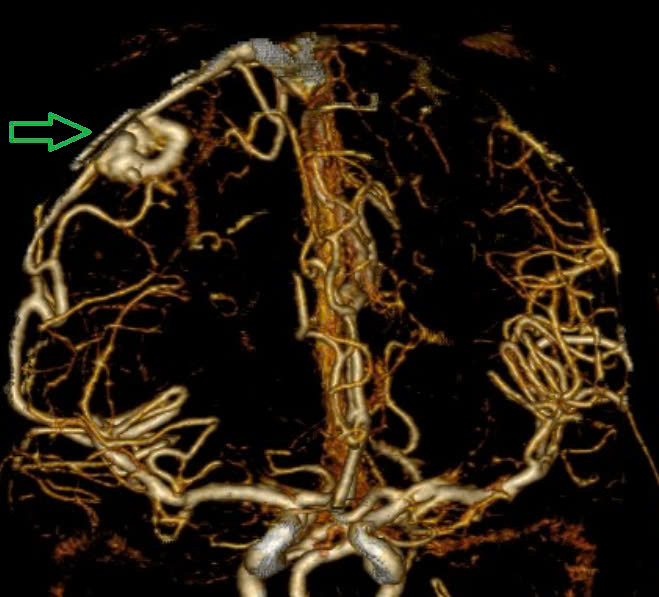

Trường hợp thứ hai: Người bệnh 19 tuổi, chưa phát hiện bệnh lý gì trước đó, đến Trung tâm Đột quỵ, Bệnh viện Bạch Mai vào những ngày đầu năm 2025 trong tình trạng co giật, hôn mê sâu, Glasgow 6 điểm, thở máy qua ống nội khí quản, liệt tứ chi. Kết quả chụp phim MSCT mạch não: Hình ảnh chảy máu não thùy đỉnh chẩm bên trái và não thất - phù não lan toả do vỡ ổ dị dạng AVM thuỳ đỉnh chẩm trái (điểm Spetzler- Martin 3 điểm). Bệnh nhân đã được phẫu thuật hút khối máu tụ và lấy ổ dị dạng mạch não. Hiện tại, bệnh nhân vẫn đang điều trị tích cực tại khoa Hồi sức Ngoại, tiên lượng khả năng hồi phục hạn chế.